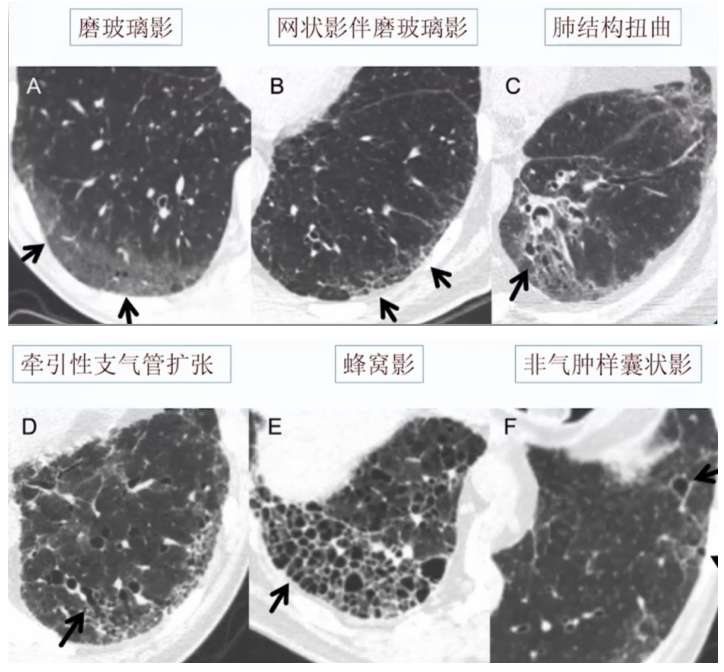

首先需要明确的是,间质性肺异常(interstitial lung abnormalities,ILA)不是独立的疾病实体,而是一种现象,其与间质性肺疾病(interstitial lung diseases,ILD)不同。ILA是一种通过胸部CT偶然发现的非重力依赖性的异常改变,典型的胸部CT表现包括:磨玻璃影或网状改变、肺结构扭曲、牵拉性支气管扩张、蜂窝样改变、非气肿性囊性变,等(图9)。病变至少涉及5%的肺区域,上、中、下肺区域由主动脉弓下缘和右下肺静脉界定。需要强调的是,ILA均为无症状,非可疑ILD患者。结缔组织病(connective tissue disease,CTD)以及家族性ILD等高危人群筛查的临床前异常、临床已知ILD患者发现的CT异常不属于ILA。

图源:Radiology, 2021, 301(1):19-34.ILA的分型:①非胸膜下,非纤维化(non-subpleural):磨玻璃影、网格,但无明显胸膜下分布;②胸膜下,非纤维化(subpleural non-fibrotic):磨玻璃影、网格,具有明显胸膜下分布特征,但无纤维化证据;③胸膜下纤维化(subpleural fibrotic):牵拉支扩、结构破坏和蜂窝,提示局部肺纤维化(图10)。临床中也要注意鉴别诊断,胸部CT易误诊为ILA的情况包括:小叶中心结节,重力依赖性异常和吸气不足,骨赘相关病变,尖帽征和胸膜肺实质弹力纤维增生症(PPFE)样病变,误吸,感染或炎症后改变,确诊的ILD肺炎、CTD-ILD、血管炎或肉芽肿相关性ILD、过敏性肺炎、职业性粉尘吸入、结节病、肺朗格-汉斯细胞组织细胞增多症、药物相关性肺炎。(1)小叶中心结节:是吸烟相关呼吸性细支气管炎的典型表现,通常不进展,并且不引起纤维化(图11)。(2)重力依赖性异常:图12所示为一例72岁类风湿关节炎男性患者的胸部CT,仰卧位CT示胸膜下肺区域的磨玻璃样异常,俯卧位CT示胸膜下区域磨玻璃异常已消失,可见右肺中叶(箭头)处磨玻璃改变,为一过性肺不张。图源:Radiographics, 2022, 42(7):1925-1939.(3)吸气不足:图13所示为一例87岁女性患者,A、B示胸膜下和肺中央区域磨玻璃样异常(箭头)。气管膜部前凸(A箭头)和血管的弯曲(圆圈)提示进行胸部CT检查时吸气不足。图C、D为随访CT,可见磨玻璃样异常消失,气管呈正常圆形(C箭头)。弯曲血管(圆)消失,与A和B相比,肺容量明显改善。图源:Radiographics, 2022, 42(7):1925-1939.(4)脊柱旁局灶纤维化:骨赘引起邻近肺组织的局灶性纤维化可以引起胸膜下肺泡间隙的慢性塌陷和纤维化(图14)。图源:Korean J Radiol, 2021, 22(3):454-463.(5)PPFE:患者胸部CT可见双上肺和胸膜下致密实变,上肺边界不规则(箭头),随访无变化(图15)。图源:Radiographics, 2022, 42(7):1925-1939.(6)误吸:误吸患者的胸部CT也会出现磨玻璃影,需与ILA相鉴别。图16所示为一例皮质基底节变性的64岁男性患者存在误吸,图A显示下肺叶双侧中央气道阻塞(箭头)和小叶中心结节(箭头),图B显示肺底水平CT示胸膜下区域和周围小叶中心结节(箭头)的磨玻璃样异常(箭头)。图源:Radiographics, 2022, 42(7):1925-1939.(7)职业相关肺纤维化:图17所示为一例诊断为有石棉肺和石棉相关的胸膜斑块患者,有长期接触石棉史;HRCT显示双侧胸膜下网状、蜂窝状和牵引性支气管扩张(箭头),纵隔窗显示双侧多发性非钙化胸膜斑块(箭头)。图17 一例诊断为有石棉肺和石棉相关的胸膜斑块患者图源:Korean J Radiol, 2021, 22(3):454-463.